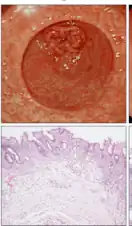

Atrophic gastritis -

Atrophic gastritis under low power. H&E stain. -

Histopathology of antral mucosa with atrophy. H&E 10x. Antral gastric mucosa with accentuated atrophy because replacement by extensive intestinal metaplasia. -

Histopathology of fundic mucosa with atrophy. H&E 10x; square 20x. Fundic-corporal gastric mucosa with extensive loss of gastric glands, partially replaced by pseudo-pyloric metaplasia.